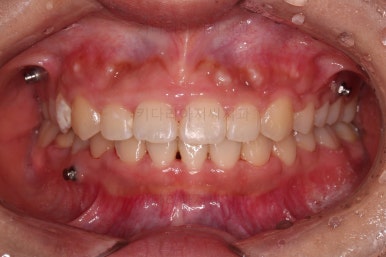

얼굴모습 포함 전후사진을 비교해 보겠습니다.

부산옥니교정 통해 많은 점이 개선이 되었네요.

과개교합 개선

웃는 모습에서 잇몸웃음(거미스마일) 개선

교합 개선

아래 앞니가 3개였으나 정중선이 맞아보이게 마무리

옥니 개선

웃는 모습 개선

물론 난이도가 매우 높은 치료라 기간은 비교적 오래 걸린 편인데요.(총 33개월)

키다리아저씨치과도 환자분도 매우 만족스러운 치료였습니다.